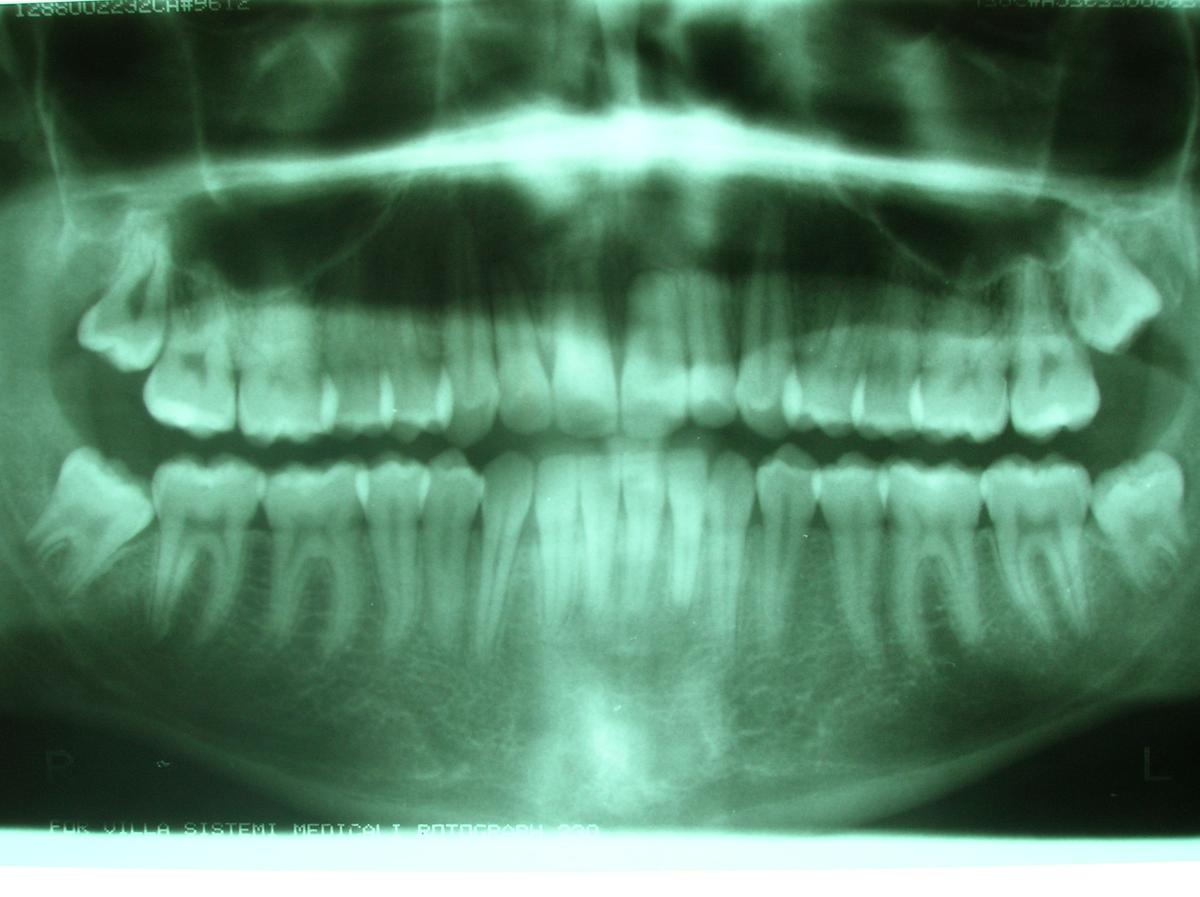

Muelas del juicio radiografia panoramica

El 10 o 25% de Norteamericanos con ancestros europeos les falta un tercer molar. Para los afroamericanos y los asiáticos-americanos, la cifra es de 11 al 40%. Sin embargo, existe un grupo de personas que vive en las regiones árticas de Canadá, Groenlandia y Alaska, el porcentaje es el más alto: Un 45% de ellos no tienen muelas del juicio.